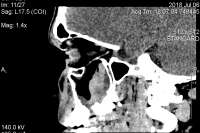

>>752738Сделал рентген, врач назначил мометазон. Сказала, ситуация как при обычном насморке. Что ещё можно сказать по снимку?